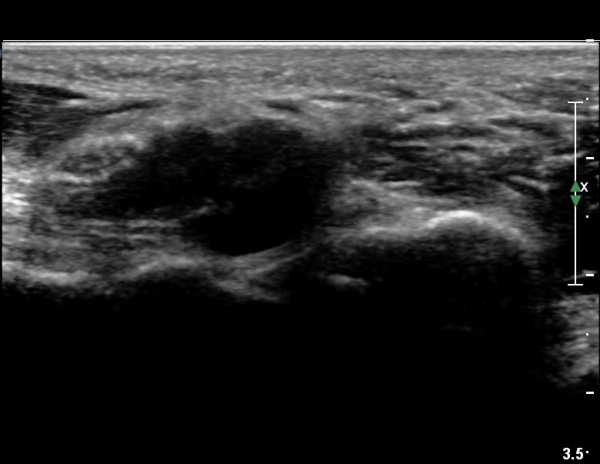

4 sono.jpg

¼Õ¹Ù´Ú ºÎÀ§¿¡¼­ ô°ñ½Å°æ ½ÉºÎ °¡Áö º´Áõ

(periphral neuropathy  of  deep palmar branch of ulnar nerve at palm level).